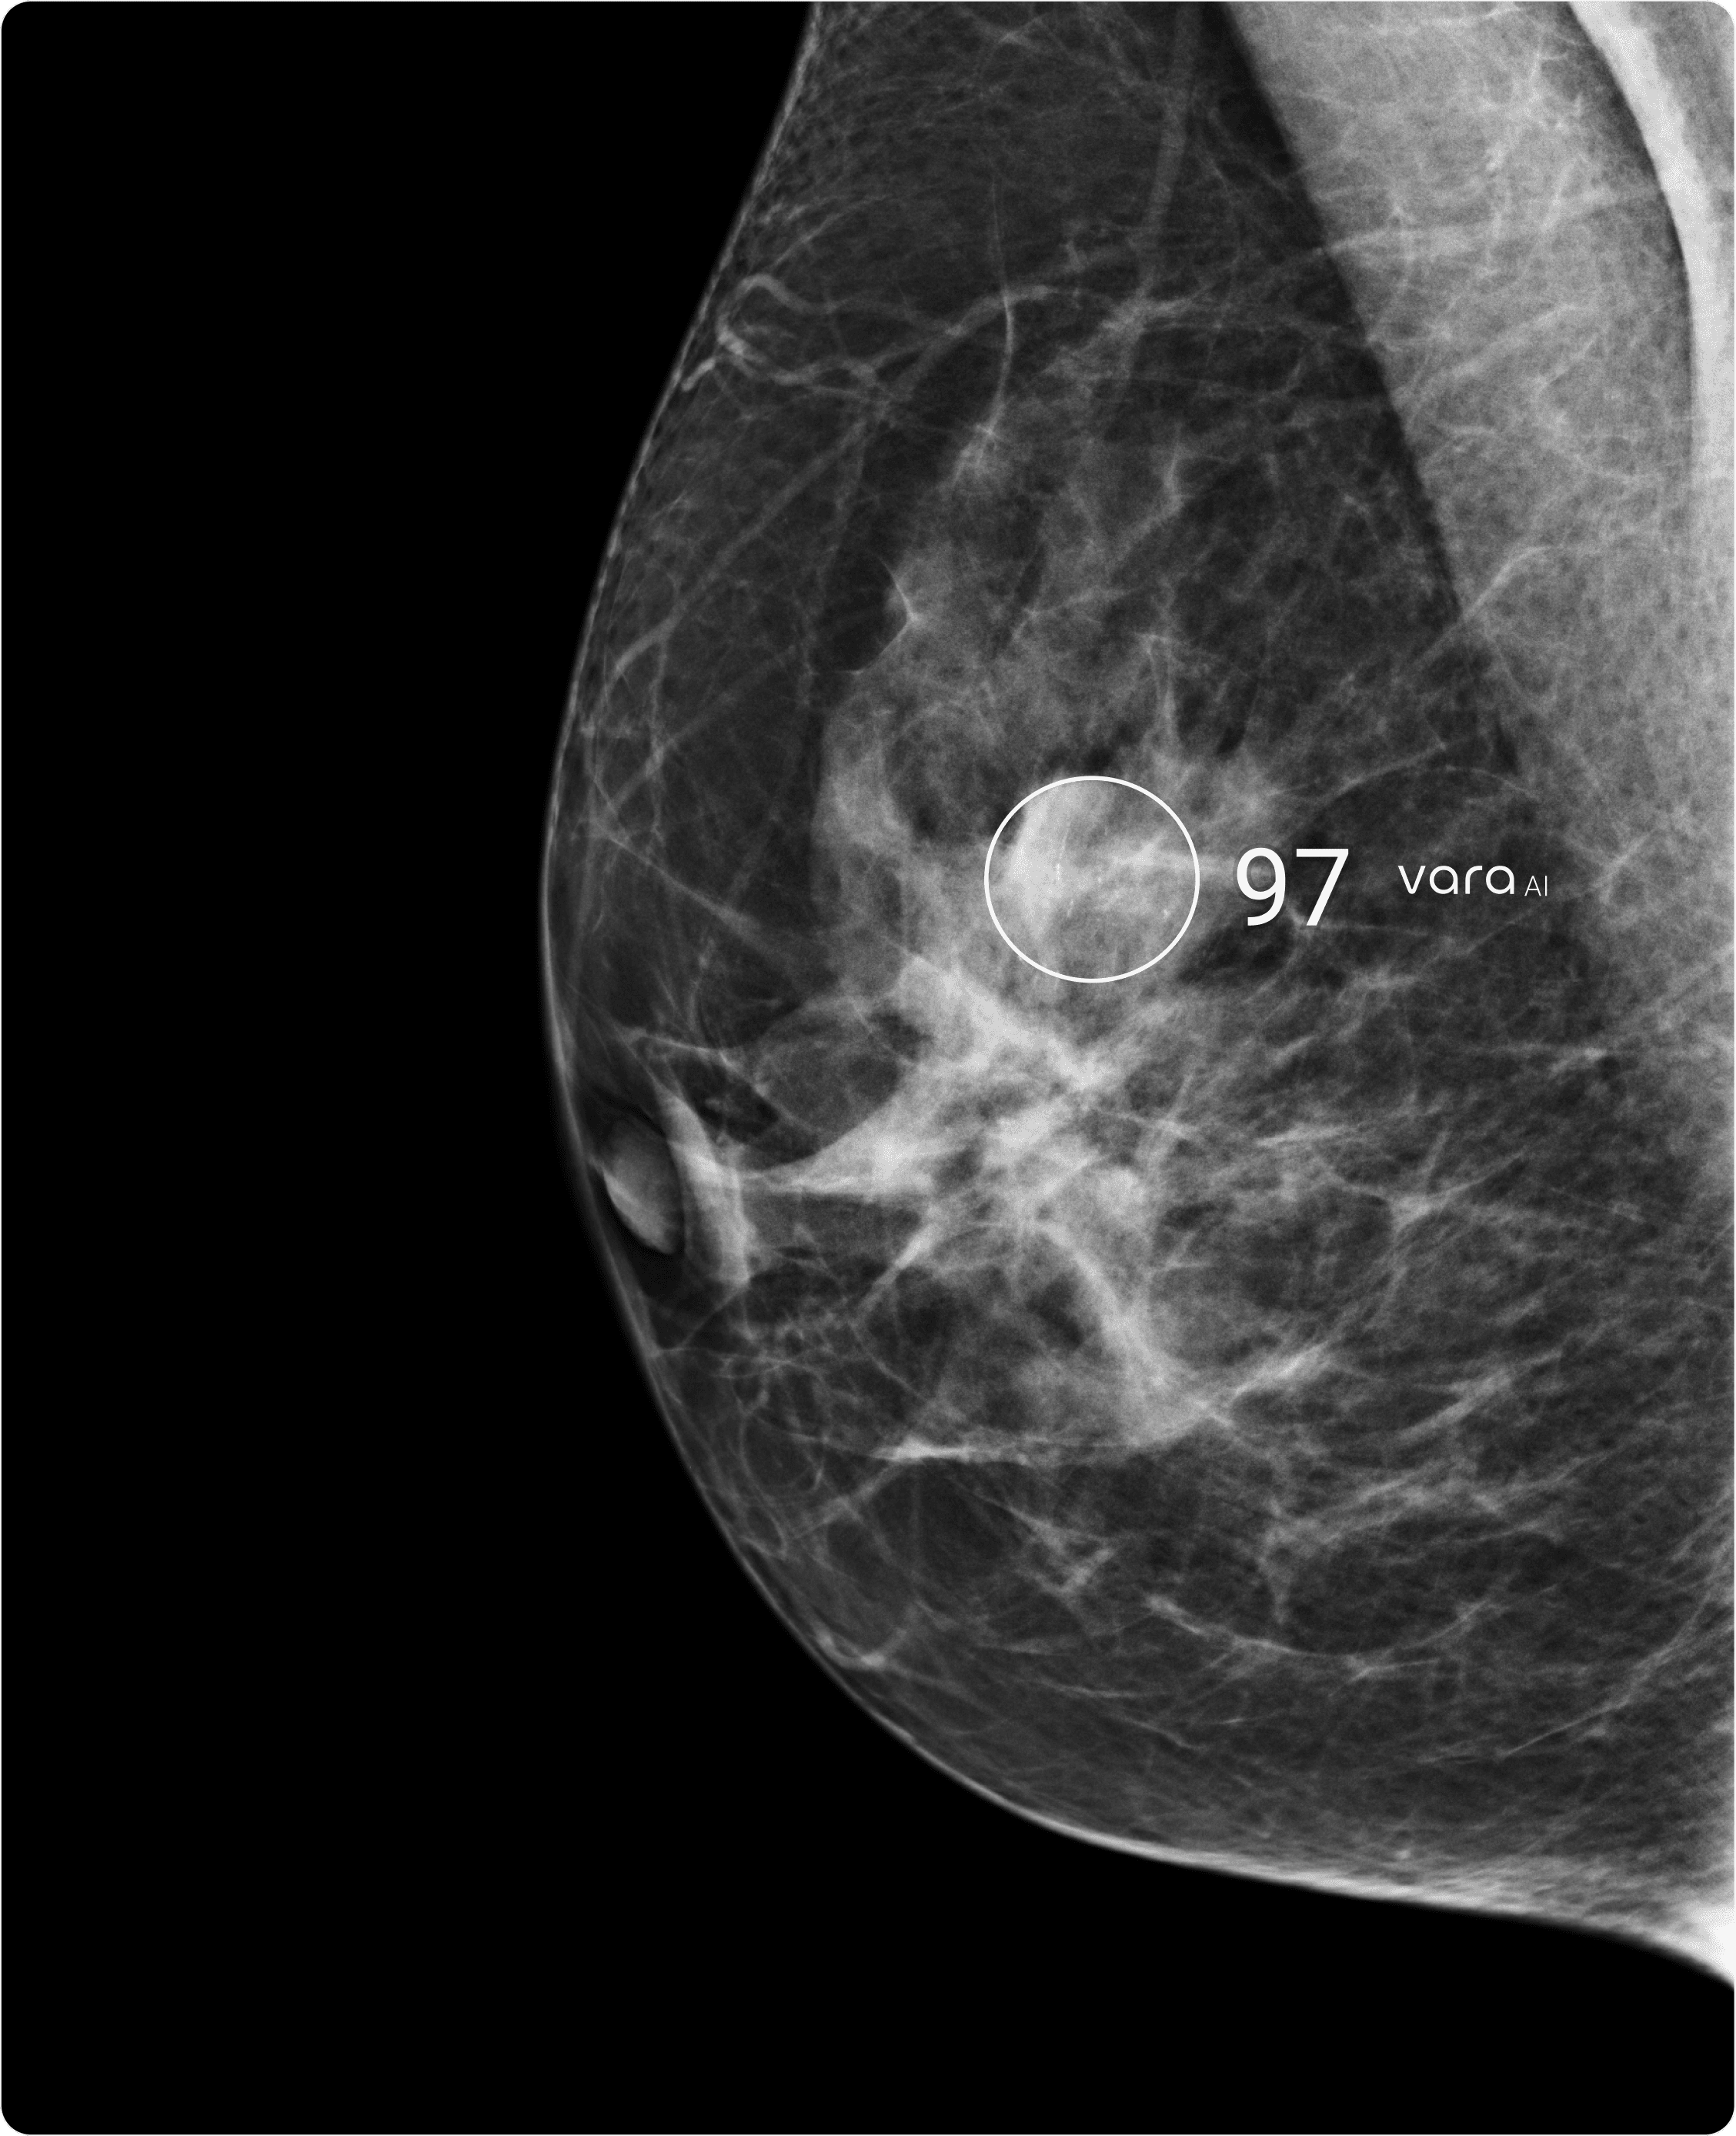

CAD-SR & Lesion Scores

Lesion markings and per-lesion scores provide precise guidance for interpretation and prioritization.

Exam-Level AI Score

Overall exam assessment (0–100) indicates how suspicious the AI considers the findings.